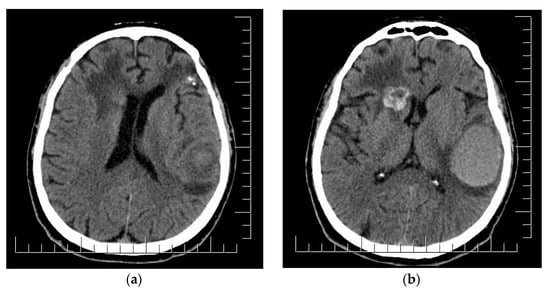

2. Case Presentation